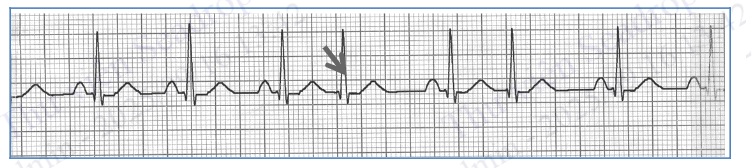

Hình 4.71. Cơn tim nhanh thất với phức bộ QRS giãn rộng

Các hình thái rối loạn nhịp thất khác

Cuồng thất: điện tâm đồ về cơ bản giống tim nhanh thất nhưng tần số tim rất nhanh > 300 ck/phút.

Xoắn đỉnh: phức bộ QRS giãn rộng, đa hình thái, trục QRS liên tục thay đổi, dường như xoắn quanh đường đẳng điện.

Rung thất: các sóng P, Q, R, S, T biến mất, thay bằng các sóng rung (f) to nhỏ, ngoằn ngoèo trên điện tâm đồ.